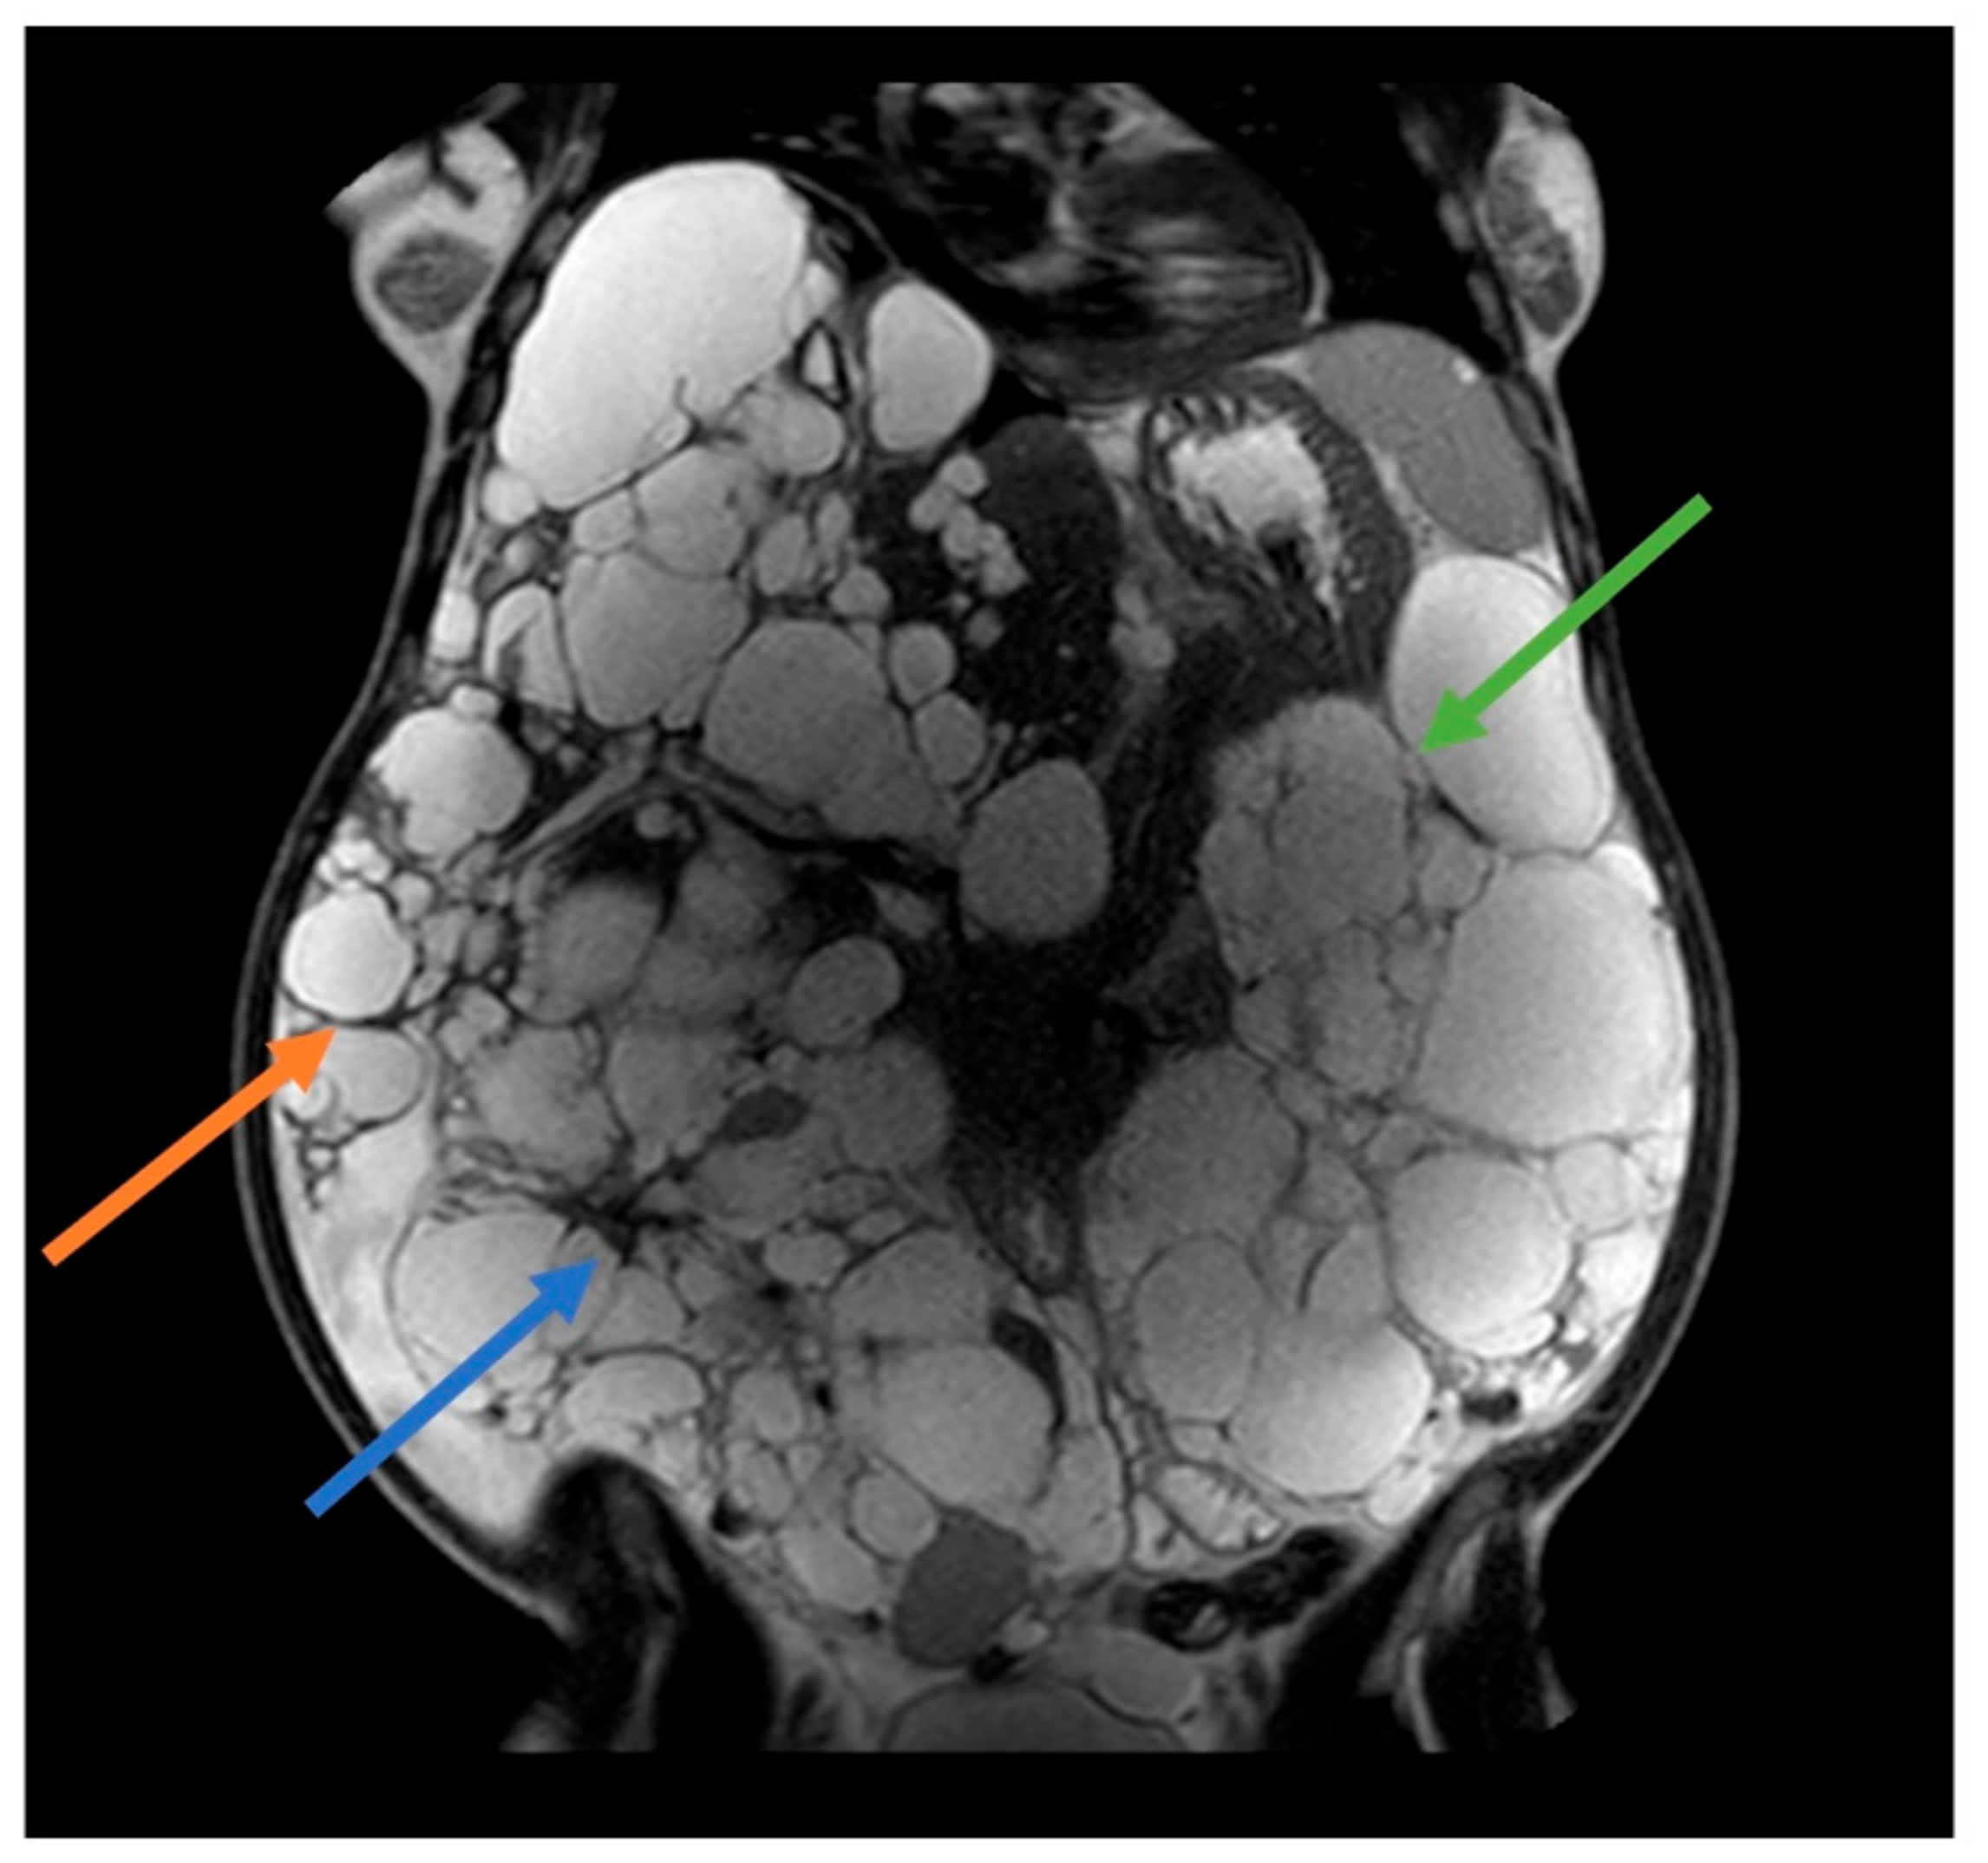

Most women develop liver cysts by age 60, particularly those with a history of pregnancies and/or estrogen-progestin therapy for contraception. A prospective study in postmenopausal women with ADPKD revealed the crucial role of estrogen in hepatic cystogenesis and increased liver volume, establishing it as a primary contributing factor [8]. Hormonal changes during pregnancy, specifically increased levels of estrogen and progesterone, may contribute to liver cyst enlargement and kidney cyst growth to a lesser extent. Additionally, increased renal blood flow during pregnancy could exacerbate cyst growth (Figure 1). It is worth noting that the effect of pregnancy on ADPKD can differ among individuals. Certain women may observe a marked increase in cyst size, whereas others may exhibit no notable alteration [9].

Figure 1.

41 years old ADPKD women with nephromegaly and hepatomegaly. Two previous pregnancies and 5 years of estroprogestinic pill. Mayo Class 1 E. Orange arrow: lower margin of the right hepatic lobe; blue arrow: right kidney; green arrow: left kidney.